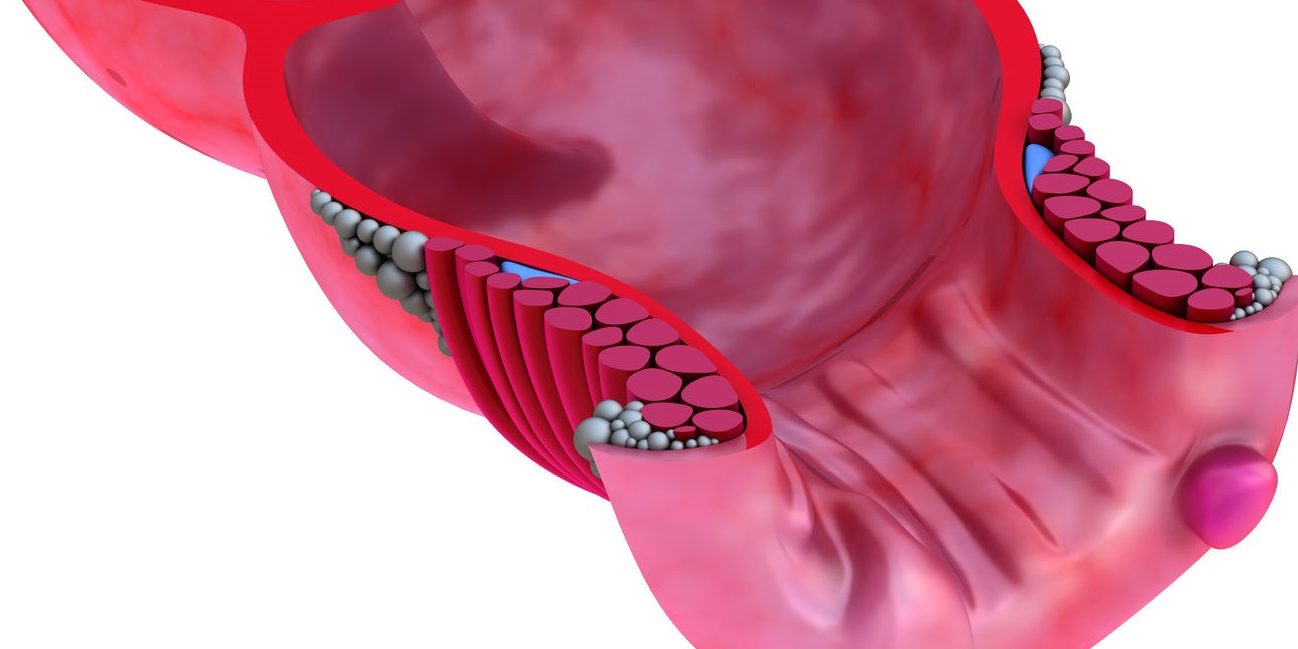

Μια ραγάδα του πρωκτού είναι ένα πρωκτικό δάκρυ ή ρωγμή, στην επένδυση του πρωκτικού καναλιού, μια κοπή ή σχίσιμο στον πρωκτό που εκτείνεται μέσα στον πρωκτικό σωλήνα.

Οι περισσότερες ραγάδες πρωκτού είναι μικρότερες από το ένα εκατοστό, αλλά ο πρωκτός είναι ένα πολύ ευαίσθητο μέρος του σώματος. Ως αποτέλεσμα, ένας πόνος στην περιοχή αυτή μπορεί να είναι αρκετά σοβαρός, ακόμη και με μια μικρή ραγάδα.